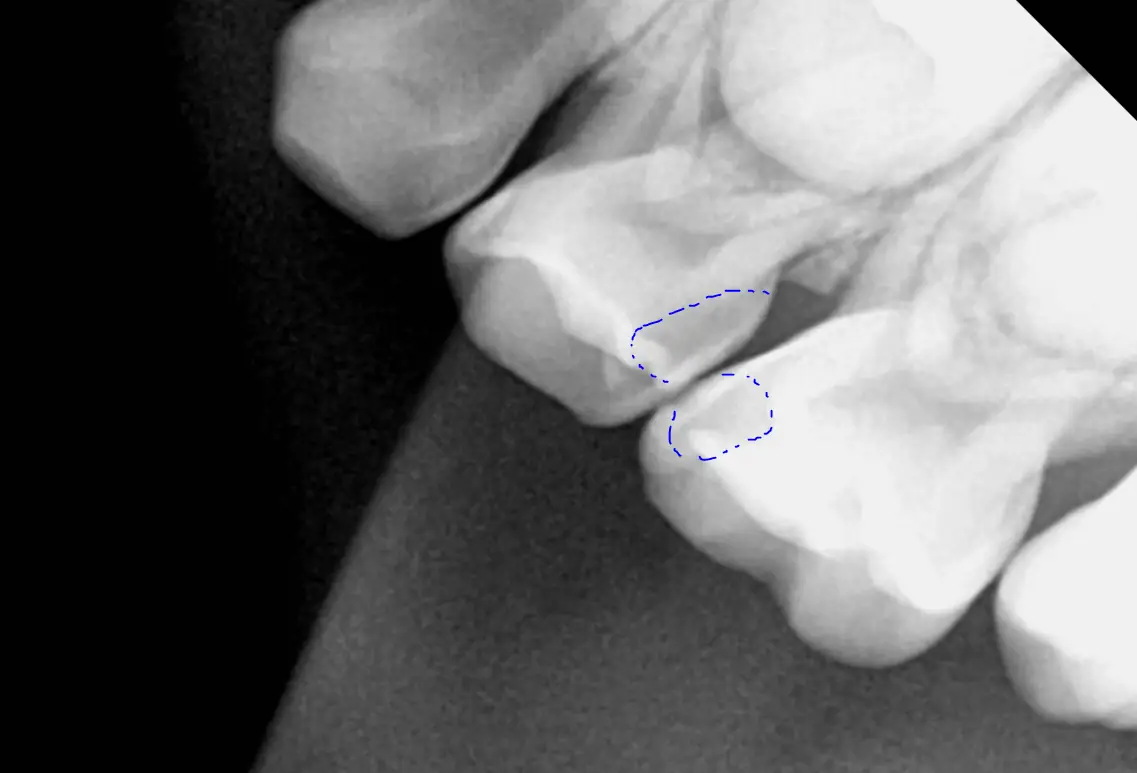

사례를 보면, 겉으로는 충치가 없어 보여도 엑스레이를 통해 충치가 상당히 진행된 상태임을 알 수 있었어요. 만약 방치했다면 신경치료까지 필요했을 수도 있죠. 그래서 정기 검진과 엑스레이 촬영이 꼭 필요하답니다.

아이들의 충치는 눈으로 쉽게 확인되지 않는 경우가 많아서 정기적인 엑스레이 촬영이 매우 중요합니다. 특히 치아 사이에 생기는 인접면 우식은 눈으로는 잘 보이지 않아, 충치가 심하게 진행되기 전에는 발견이 어렵죠.